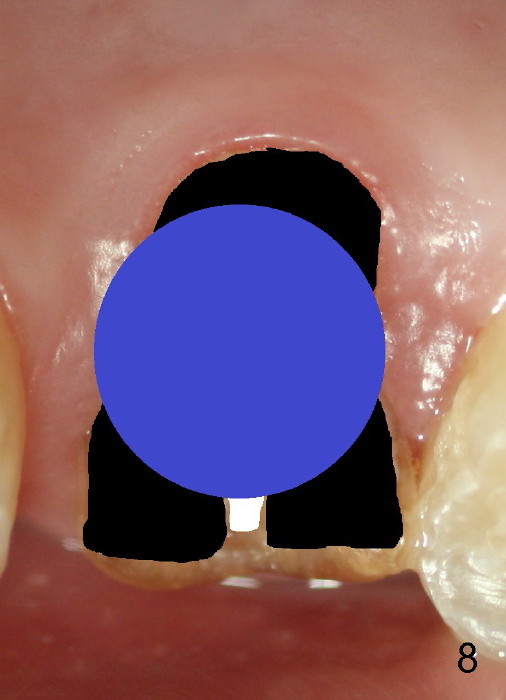

The 1st approach is used for the following case: a 46-year-old man with #14 (Fig.1). The root stumps are large and relatively close to each other (Fig.2 mirror view) so that when the roots are extracted (Fig.3 black), the septum is narrow (white). A 1.2 mm pilot drill penetrates the septum (red).

By the time a 2.6 mm bone expander is used, the septum starts to break off (Fig.4 green). The osteotomy site has to be changed: first to the palatal slope of the palatal socket (red) with the coronal end of the drill leaning buccally. Suddenly a better idea occurs: new osteotomy remains in the palatal socket, but as buccally as possible (blue) and finishes with rounded tapered osteotomes 2-4 mm at ~17 mm deep. The coronal end of the osteotomes is controlled to be positioned in the center of the socket (Fig.5 blue).

Fig.6 shows 4.5 mm tap in place with stability. It appears too high. When it is removed, the sinus membrane is found to have been perforated. The next taps (5,6 and 7 mm) are placed shorter by 3 mm with stability. A piece of collagen dressing and a small amount of bone graft (Fig.7 *) are inserted to the osteotomy before placement of a 7x14 mm implant.

Fig.8 illustrates the implant (blue) placed in the middle of the socket. The remaining buccal and lingual gaps (black) are then closed by graft and membrane. Placing the graft in the deeper portion of the mesiobuccal socket is not so easy because the large implant blocks the entrance (Fig.7 between lower arrowheads). If more graft has been dispensed and the earlier PA shows larger upper space exists (Fig.6 between upper arrowheads), the graft should be placed to that region prior to implant placement.